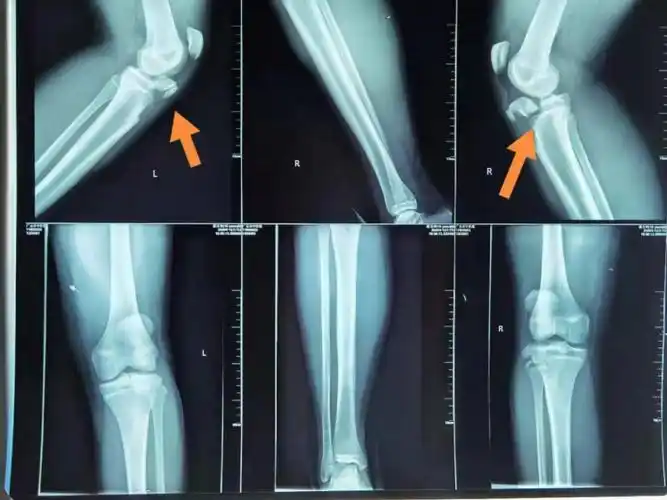

体育课跑步初中生双侧胫骨结节骨折医生呼吁加强青少年日常运动